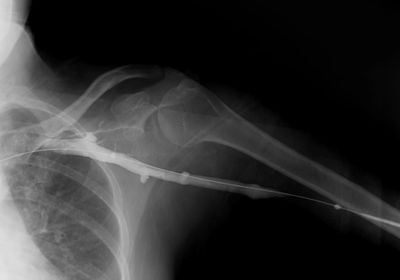

At Pathway Imaging, we offer advanced fluoroscopy imaging to provide real-time, moving X-ray images of your body. This technology allows physicians to see organs, joints, and systems in motion, making it a valuable tool for both diagnosis and image-guided procedures.

Fluoroscopy uses a continuous X-ray beam and special imaging equipment to create a “live” video of the inside of your body. Unlike a traditional X-ray, which captures a single still image, fluoroscopy shows movement—helping doctors observe function, guide treatments, and perform minimally invasive procedures with accuracy.